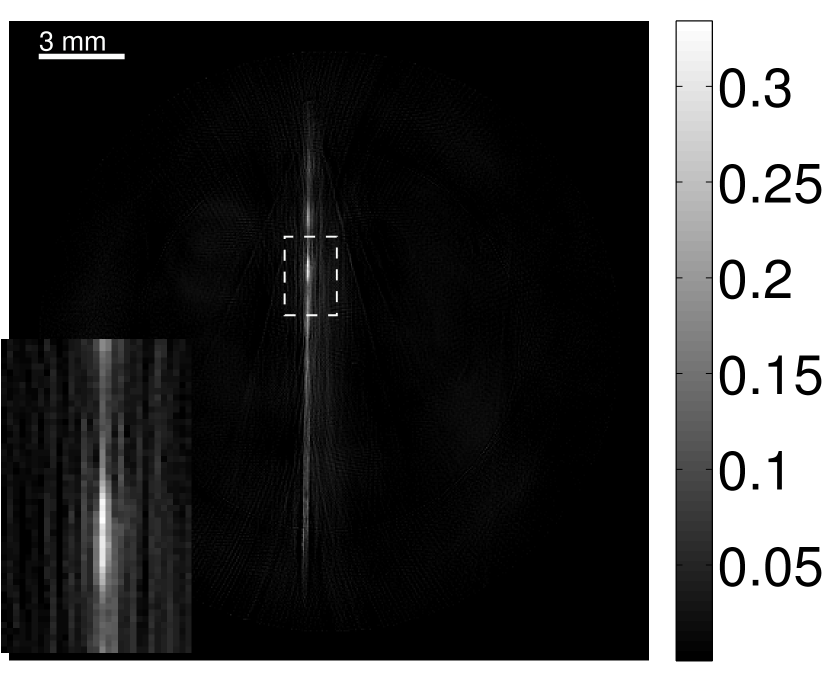

Figure 11 displays images of the needle phantom reconstructed by use of the simple backprojection method [BM2003]. Figures 12 and 13 display the images reconstructed by use of the conventional iterative method and VP algorithm, respectively.

Figures 12 and 13 show that the width of the needle in the reconstructed image increases as the regularization parameter increases for both the conventional iterative method and the VP algorithm. The images reconstructed by use of the VP algorithm appear to have a reduced noise level compared to the images reconstructed by the backprojection and conventional iterative methods, regardless of the choice of the regularization parameter values. The profile plots corresponding to these three methods are shown in Figure 14. Since the image of the coefficient vector and the EIR are recoverable only up to a multiplicative constant, every profile was normalized for comparison. These plots demonstrate that the image reconstructed by use of the VP algorithm possessed a more uniform background than those obtained by the backprojection and the conventional iterative methods.